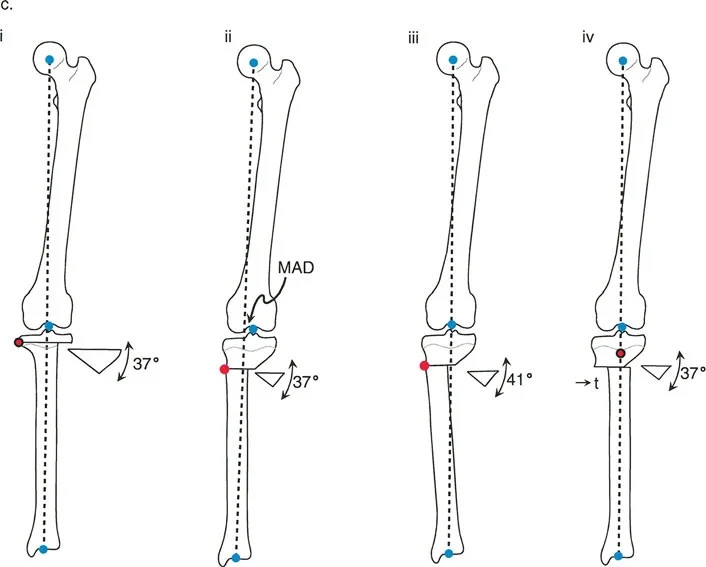

إن نجاح جراحة تصحيح تشوهات الأطراف يعتمد بشكل كبير على التخطيط المسبق الدقيق. هذا التخطيط أشبه برسم خارطة طريق هندسية تضمن أن كل خطوة جراحية تقود إلى النتيجة المرجوة. يعتمد هذا التخطيط على "مبادئ بالي" التي تحدد ثلاثة متغيرات هندسية أساسية في كل حالة:

- مركز دوران التشوه (CORA - Center of Rotation of Angulation): هذه هي النقطة المحورية للتشوه في العظم. يحددها الجراح من خلال رسم محاور الطرف قبل الجراحة.

- محور تصحيح الزاوية (ACA - Angulation Correction Axis): هذه هي النقطة التي يدور حولها الجزء البعيد من العظم لتصحيح التشوه. يتحكم الجراح في هذه النقطة عن طريق وضع المفصلات على المثبت الخارجي أو نقطة الارتكاز للوحة التثبيت.

- مستوى قطع العظم (Osteotomy Level): هذا هو الموقع الفعلي الذي يتم فيه قطع العظم. يتحكم الجراح بشكل كامل في هذا المتغير، ويتم اختياره بناءً على عوامل مثل الأنسجة الرخوة، وجودة العظم، ونوع الأجهزة المستخدمة.

النتيجة النهائية للتصحيح تعتمد كليًا على كيفية ارتباط هذه المتغيرات الثلاثة ببعضها البعض. الفشل في التخطيط الدقيق يمكن أن يؤدي إلى "تشوهات ثانوية" غير مرغوب فيها، مثل انحراف المحور الميكانيكي أو ترجمة (إزاحة) العظم.